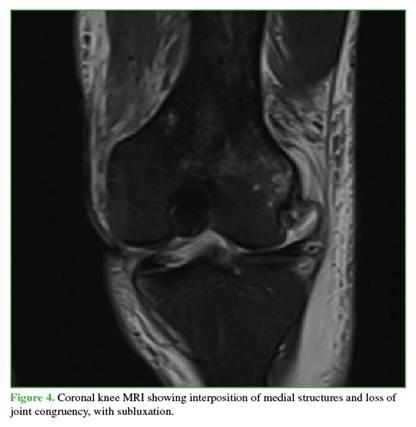

Radiographs showed widening of the medial joint space consistent with medial instability. Further imaging was obtained with magnetic resonance imaging (Figures 4 and 5) to evaluate possible interposed tissues or structures, and with CT angiography (Figure 6) to rule out vascular injury given the time elapsed since trauma. Marked edema was noted in the medial soft tissues, including the capsule and medial structures in the intercondylar region, along with persistent knee subluxation. Vascular compromise was ruled out, with preservation of the femoropopliteal vascular bundle.

A longitudinal medial approach was carried out, and the extensor mechanism was released to evaluate the articular surface of the patella and increase exposure. The medial femoral condyle was found to be completely denuded. Careful flap dissections were performed to improve visualization despite the everted patella. Through valgus maneuvers, the relevant structures were identified and localized. Attempts were made to remove the interposed meniscus, medial retinaculum, and capsule using levering techniques with different instruments, but this was unsuccessful due to tension within these structures despite reduction maneuvers. Therefore, the capsule and the patellofemoral ligament were sectioned to release the femorotibial and intercondylar space, achieving clinical reduction and congruency of the knee. Copious irrigation with saline solution was performed, followed by capsular repair and suturing of the medial patellofemoral ligament and medial retinaculum. Stability was reassessed, and the knee did not redislocate with deep flexion or extension. No chondral lesions were observed in the patella or trochlea. The medial meniscus was found to be impinged but without body or root tears; therefore, no further management was required. An articulated knee brace was applied, postoperative radiographs were obtained (Figure 7), and delayed ligament reconstruction was scheduled for 3 weeks later. During that procedure, the anterior cruciate ligament was reconstructed with an allograft; the posterior cruciate ligament was reconstructed using a single-bundle allograft technique; and the posteromedial corner was reconstructed using the LaPrade technique. At 4-week follow-up, knee range of motion was 10° to 90° of flexion. The patient continues with physical therapy.